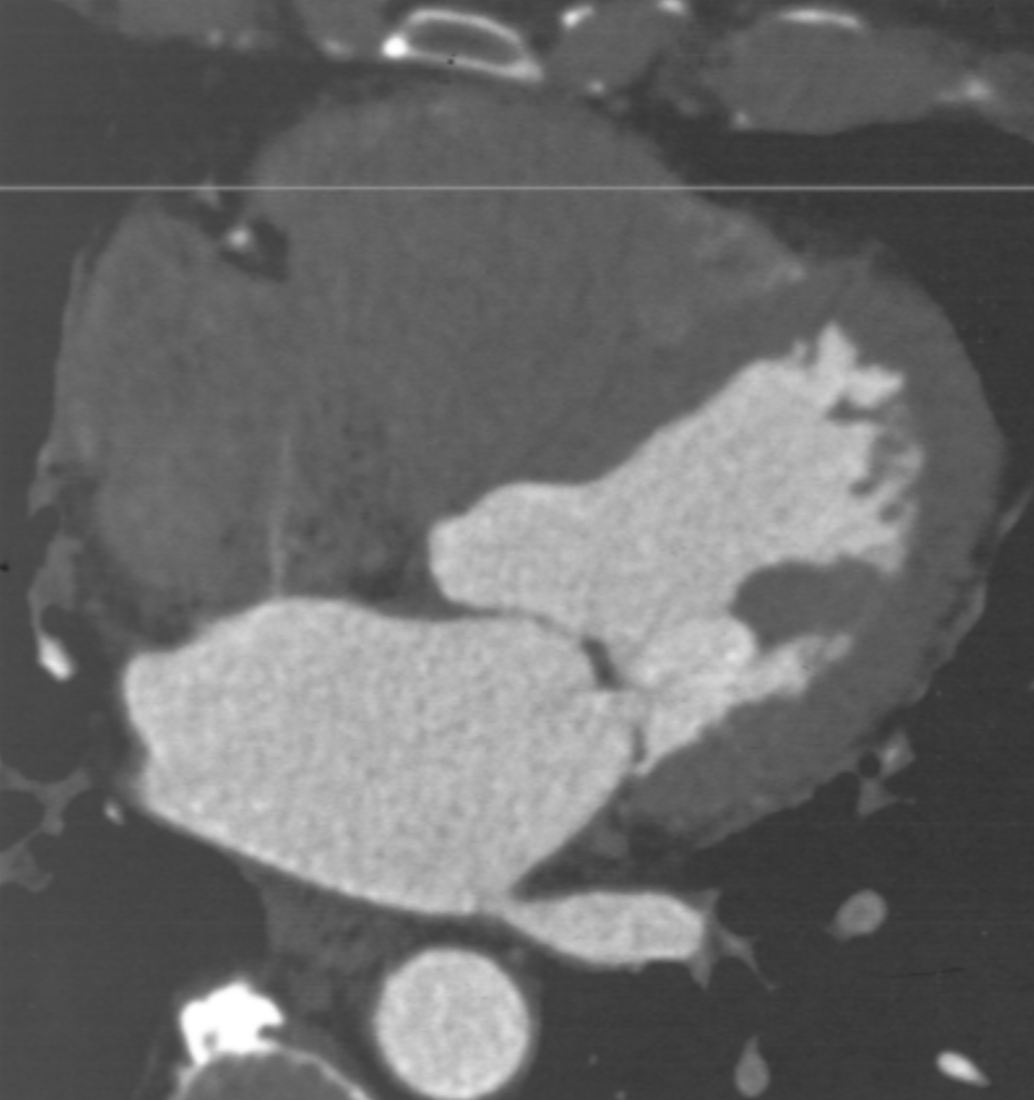

What are the characteristics of chronic infarct by cardiac CT?